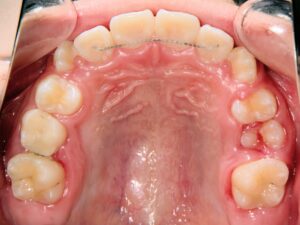

第1期治療終了時

顔貌写真

口腔内写真

治療結果

上の前歯のデコボコが改善

上の歯の狭さが改善

目標の永久歯萌出スペースを確保

第2期治療へ移行

上の前歯の裏側に保定装置(Fixリテーナー)を装着し、全ての永久歯萌出後に全顎矯正を行い、全体的な咬み合わせの調整を行います。

経過観察期間:2年7か月